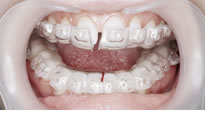

一見すると、あまり難しい反対咬合には見えませんが、実は下あごを無理に後ろに押し下げている状態で普段過ごしています。そのため、顎の関節に不具合が生じていました。

また、上顎には一部乳歯が残っているのですが、もう抜けそうになっていたので、その隙間をどうするかも問題となっていました。それに加え、上顎の2番目の永久歯(側切歯)が通常より幅が狭い「矮小歯」だったので、隙間が開いているなどの問題も重なっていました。

さまざまな問題をふくんでいたので、最新のCAD技術を応用した矯正治療分析ソフトを用いて治療計画を立てて、動画で治療経過予測を説明しています。

こちらに示しているのは治療開始時、手術直前予測、手術後予測の3段階静止画像ですが、実際のCADでは治療経過を動画で表現しています。